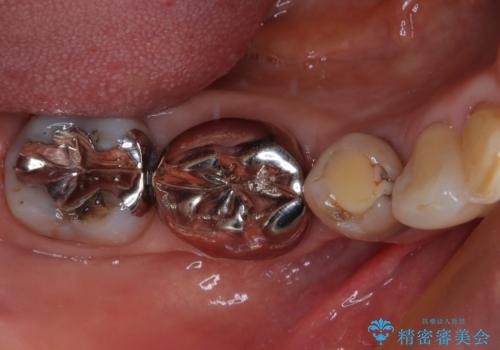

奥歯の目立つ銀歯をセラミックに オールセラミッククラウン治療

- 奥歯の目立つ銀歯と、神経が失活して変色した前歯を気にして来院された患者様です。

銀歯と歯の間に隙間があり、冷たいものがしみる知覚過敏の症状が認められたため、銀歯を白くするだけでなく、知覚過敏症状の改善も狙って補綴治療を行うこととしました。